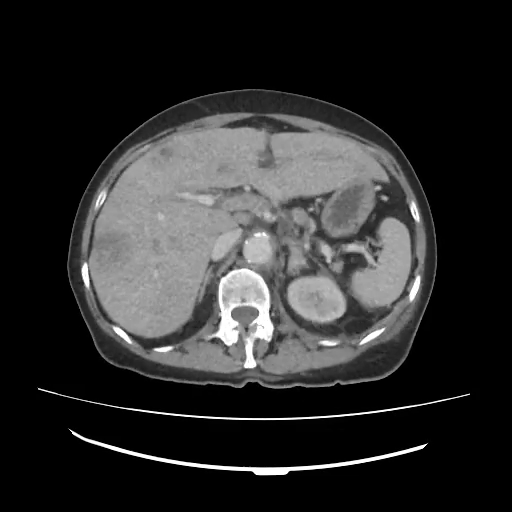

La paciente ingresa a cargo de cirugía y durante la hospitalización se le realiza TAC toracoabdominal que corrobora los hallazgos vistos mediante la ecografía, y añade linfadenopatías, una imagen de aspecto también metastásico suprarrenal izquierdo y engrosamiento focal de paredes gástricas de aspecto neoproliferativo.